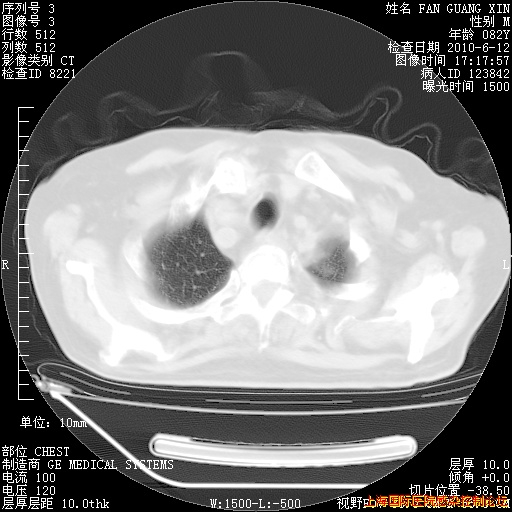

6月12日纵膈窗